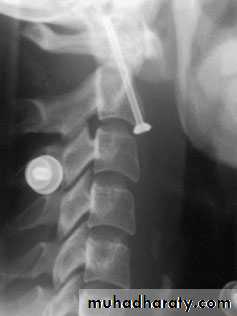

TREATMENT

If there is no neurological deficit, the patient can betreated surgically or by confinement to bed and traction

for 2–4 weeks, followed by a further period ofimmobilization in a halo-vest for 6–8 weeks.

urgent anterior decompression is considered –

anterior corpectomy, bone grafting and plate fixation,

and sometimes also posterior stabilization.